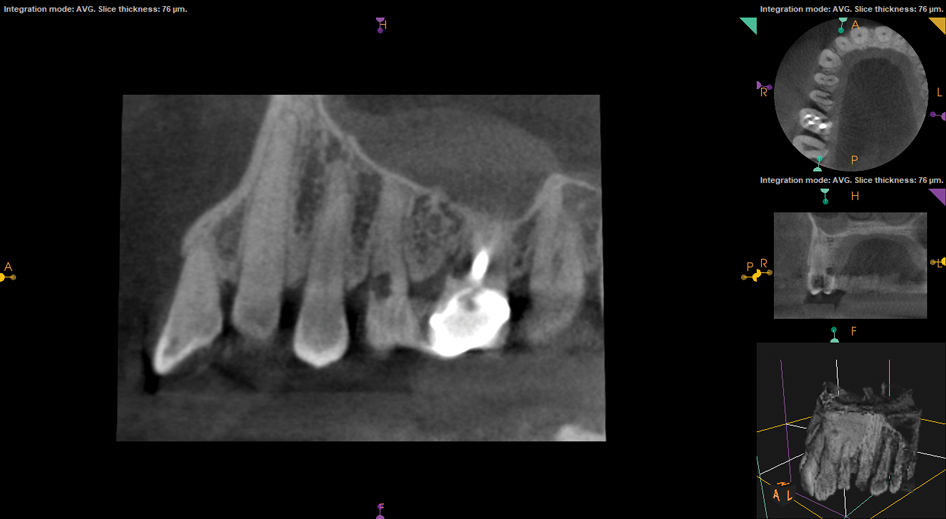

(1.) Preoperative CBCT scan showing Class 2 ECR defects on teeth Nos. 3 and 4 that were surgically accessible.

Figure 1